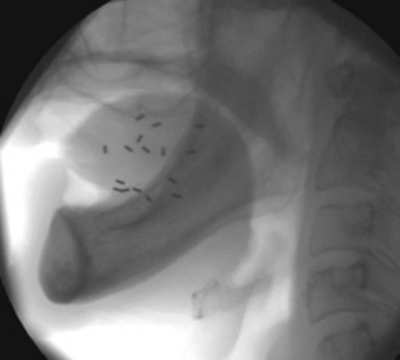

セシウム針は直径1.65mm、長さ24.5mmもしくは55mmの針状線源で、これらを5~8本程度、腫瘍(舌)に対して直接刺入します(線源の刺入は一時的で、約1週間後に取り出します)。

早期の口唇がん、口腔がんに対する密封小線源治療1"